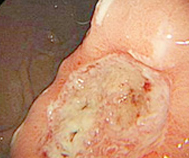

医生简介:王芸凭借其在消化内科领域的杰出贡献,多次受邀出席全国重要学术会议、论坛。为广大患者解除胃肠困扰。对萎缩性胃炎、胃溃疡、十二指肠溃疡等常见疾病具有丰富的诊疗经验...【详细】

• 无痛胃镜

• 无痛肠镜